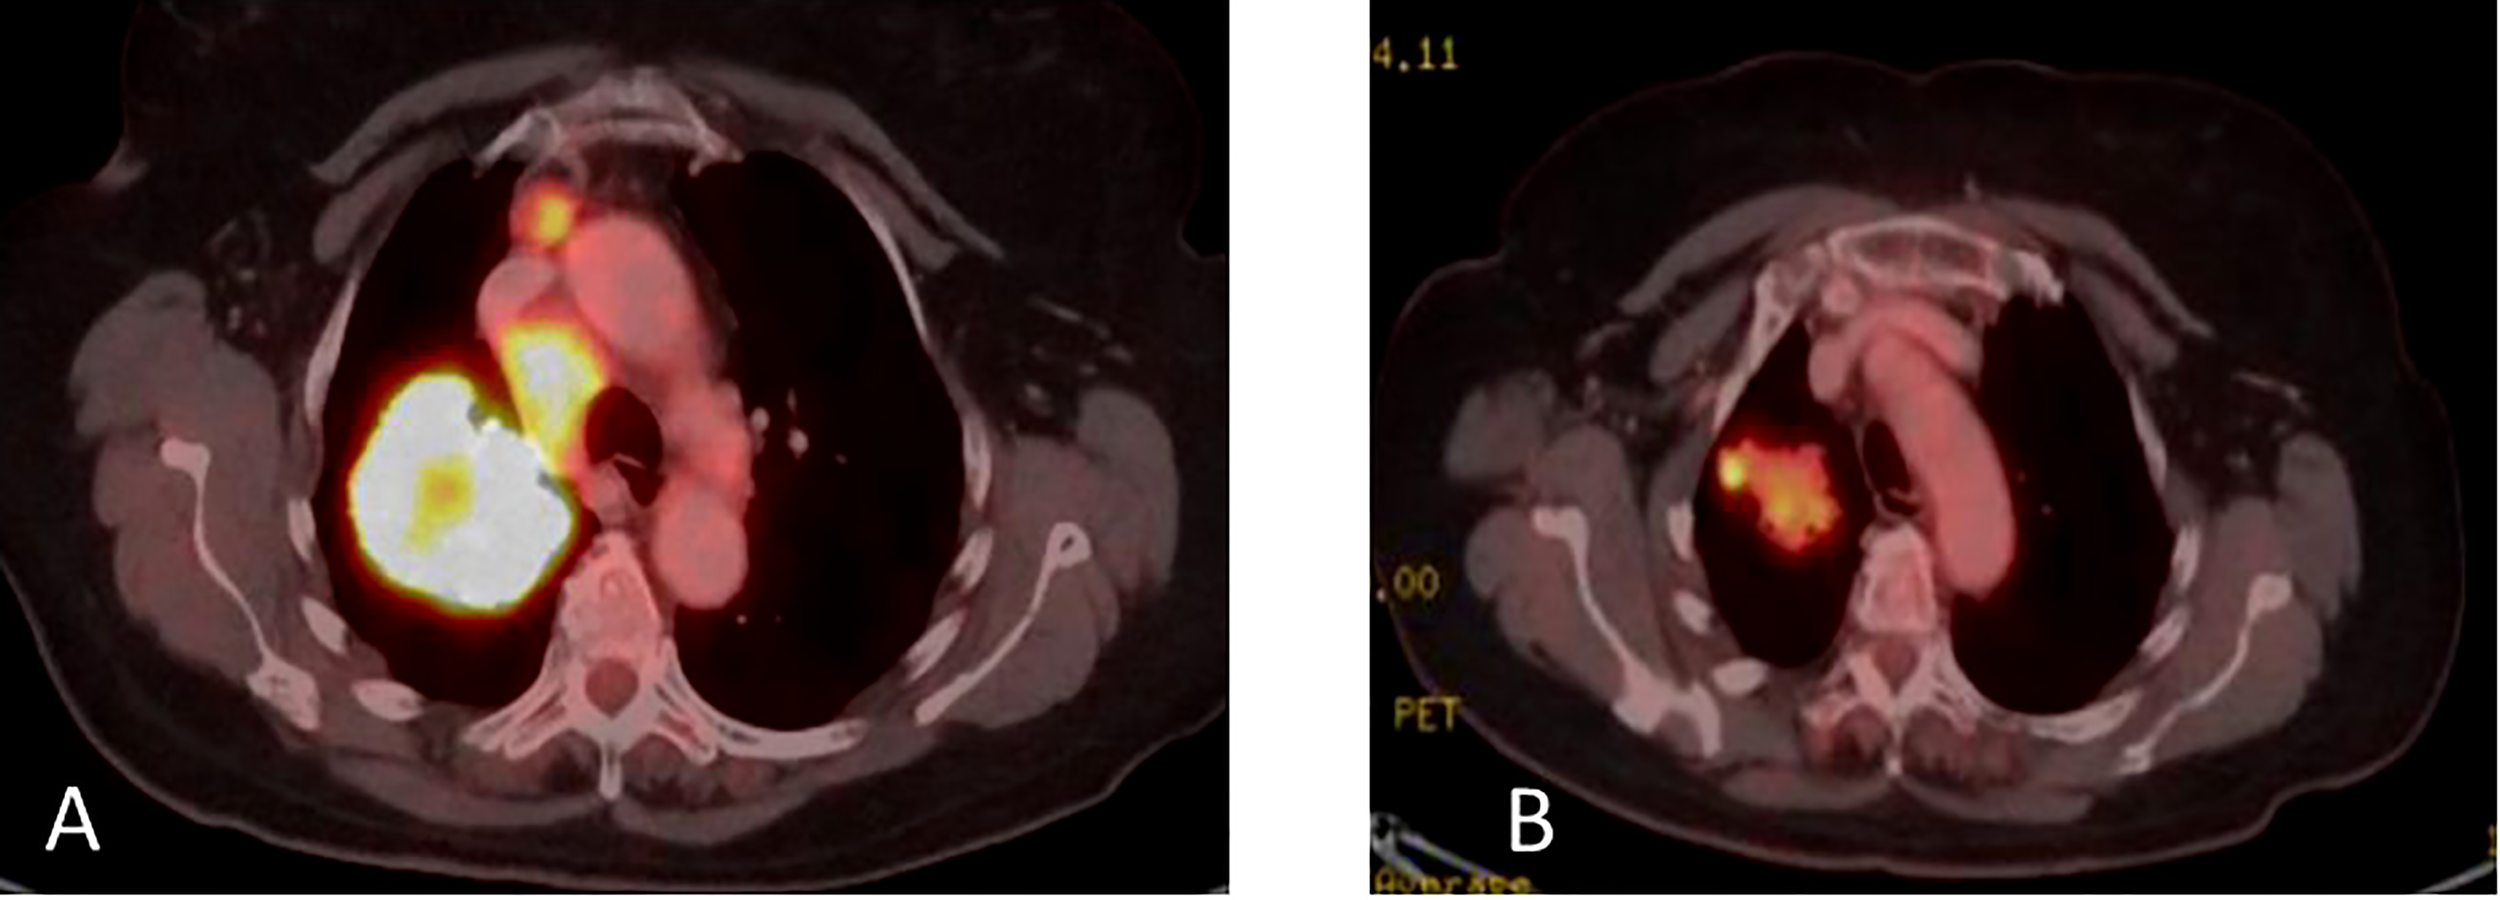

Upon disease progression in October of 2021, cfDNA liquid biopsy demonstrated EGFR L858R of 2.3%; V83L of 2.8%; with MET amplification. Brain MRI showed no metastases. Treatment with osimertinib (80mg daily) was continued. The decision was made to add 1050 mg of Amivantanab every two weeks to the patient’s treatment at this time. After four rounds of treatment, resulted in clinical and RECIST partial response (Figures 7A, B).

Figure 7

(A) Coronal PET-CT scan from October 2021 shows a left lung mass and ipsilateral pleural effusion with increased uptake of FDG-18, indicating disease progression on Osimertinib. (B) Three months later, January 2022, showed significantly decreased uptake of FDG-18, indicating partial response following adding Amivantamb to Osimertinib.

In March 2022, treatment was continued, with Amivantanab reduced from two-week intervals to three-week intervals due to grade 2 adverse events (diarrhea and paronychia). Liquid biopsy in May 2022 demonstrated total eradication of MET and EGFR from the cfDNA in the blood (Figure 8). Eight months later, the patient is still responding to the combination therapy.

Figure 8

Guardant360 response map for circulating free tumor DNA following each treatment line.